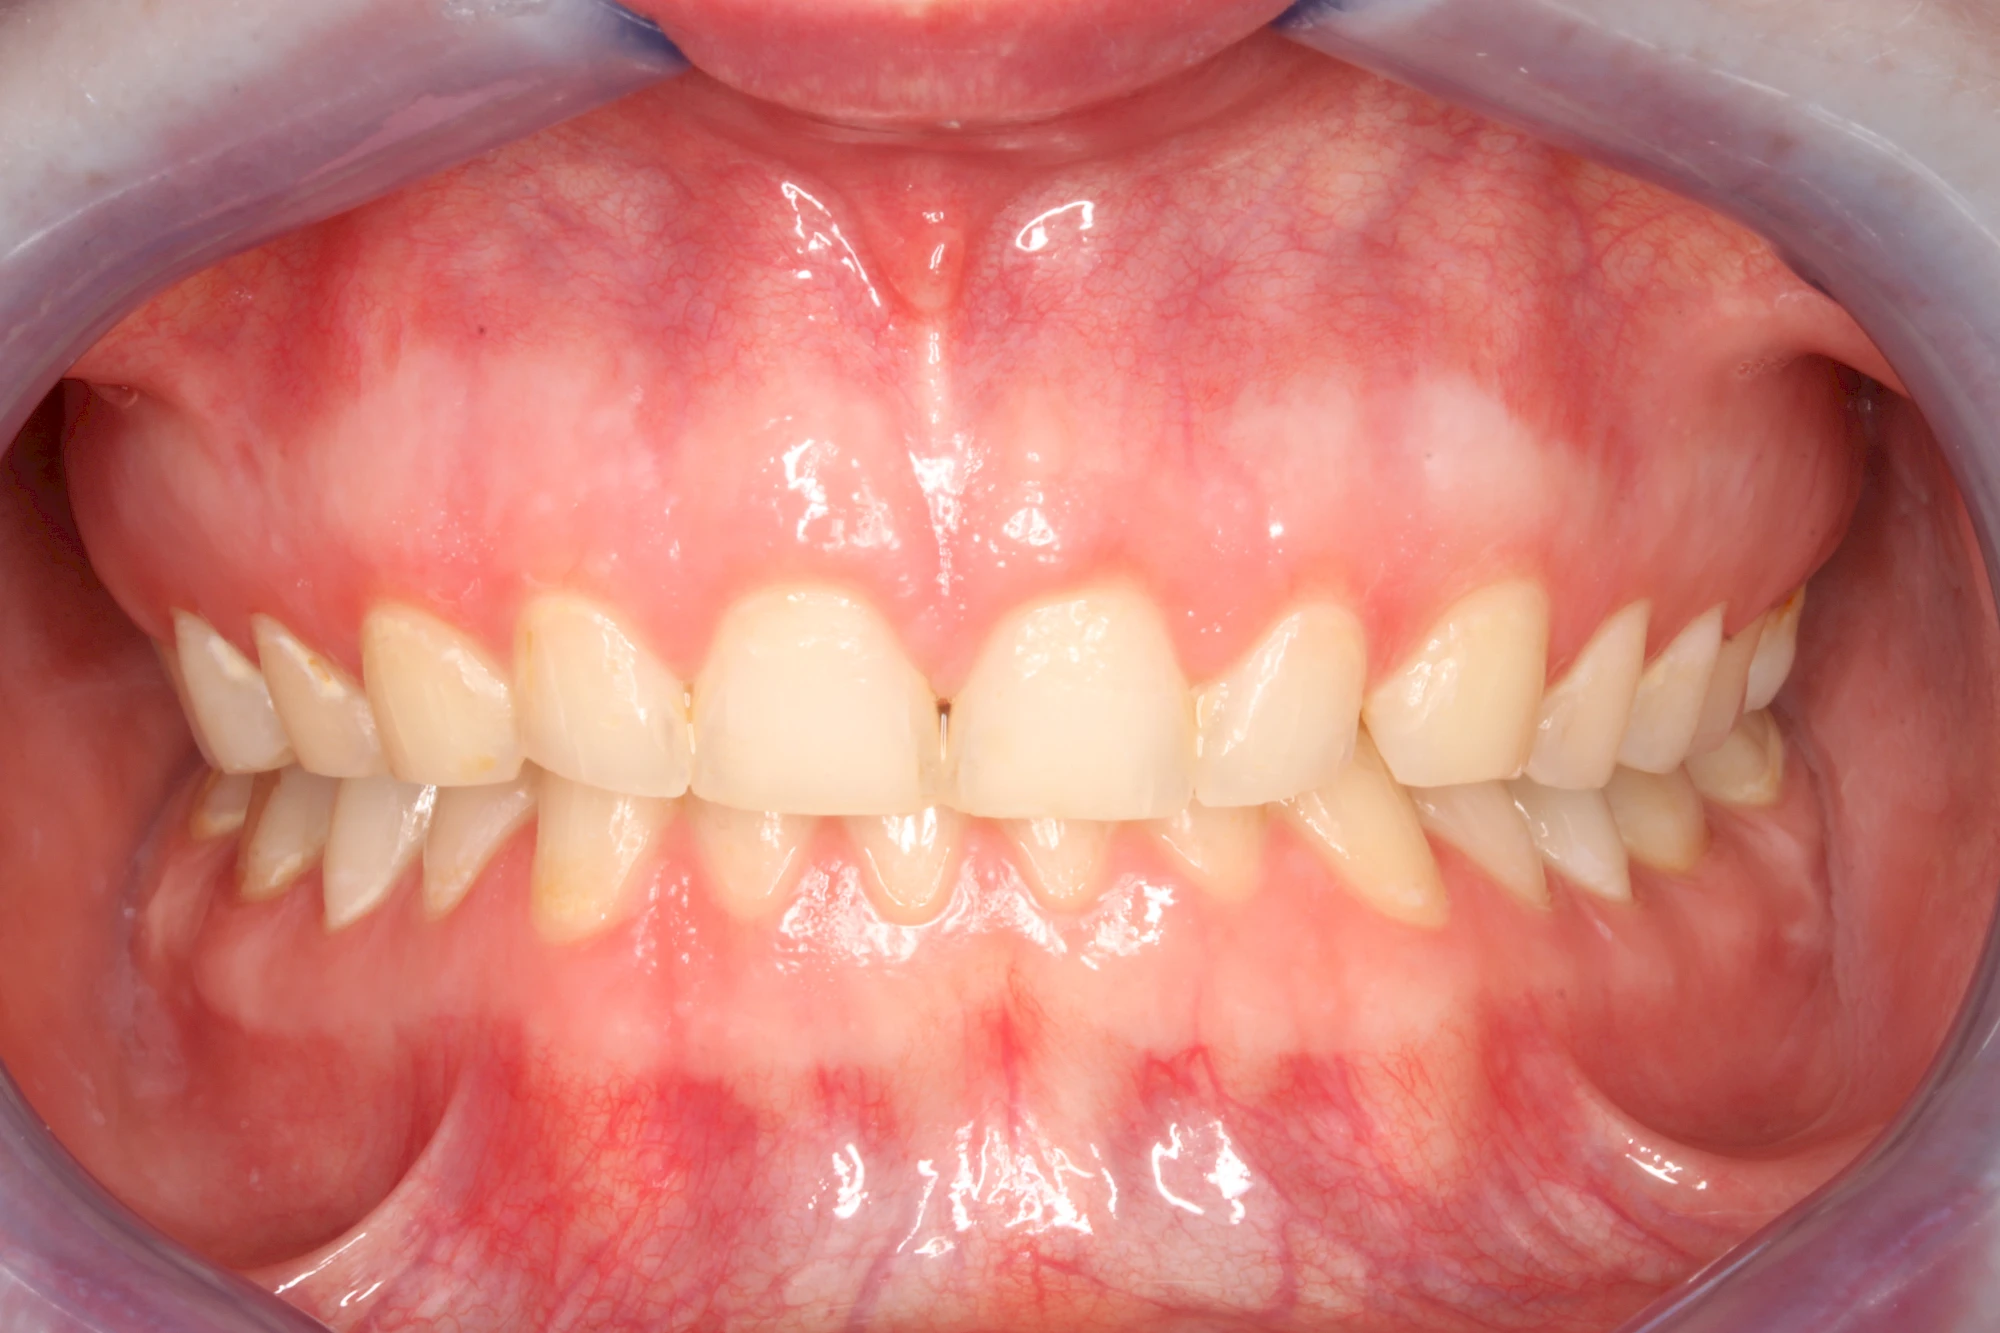

Über die Zeit können verschiedene Prozesse die Zahnhartsubstanzen aufzehren:

- Abnutzung durch Kauen (Abrasion) oder duch durch übermäßiges Knirschen bzw. Pressen (Attrition)